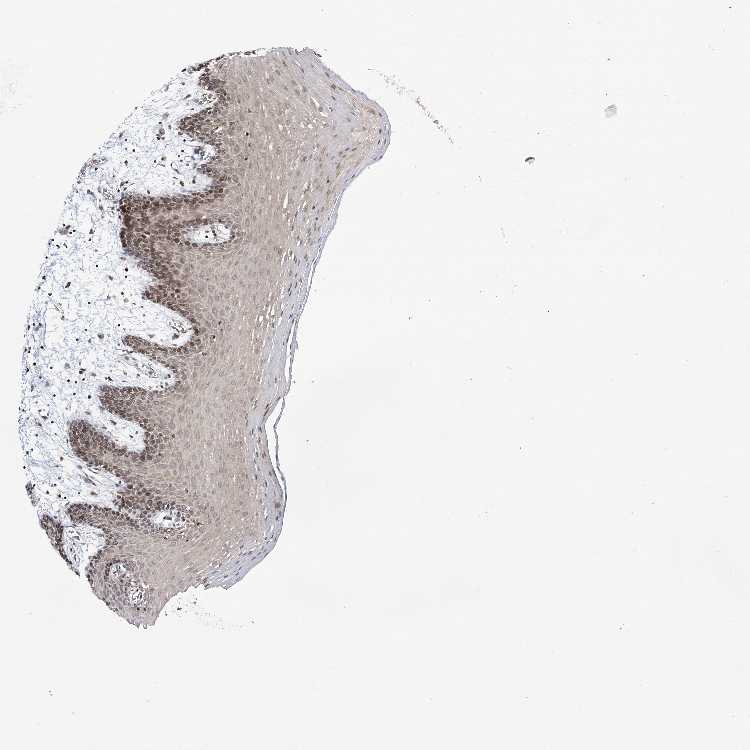

TISSUE PRIMARY DATA ORAL MUCOSA Show tissue menu

ORAL MUCOSA - Antibody stainingi

Antibody staining in the annotated cell types in the current human tissue is reported as not detected, low, medium, or high, based on conventional immunohistochemistry profiling in selected tissues. This score is based on the combination of the staining intensity and fraction of stained cells.

Each image is clickable and will lead to virtual microscopy that enables deeper exploration of all samples and also displays staining intensity scores, fraction scores and subcellular localization as well as patient and tissue information for each sample.

Antibody HPA037786Antibody HPA038034Antibody HPA038867Antibody HPA038868

Squamous epithelial cells Not detectedLowLowMedium